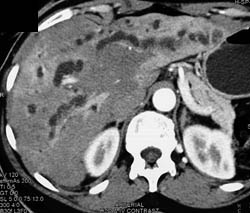

Liver Abscess